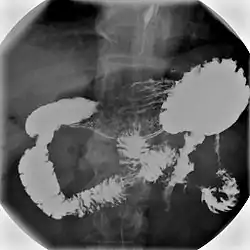

בדיקת בריום היא בדיקה רפואית שנעשית באמצעות בליעה או חוקן של תמיסת מלחי בריום שמדגימה ומשקפת את מצב דרכי העיכול, כדי לאתר בעיות כמו דלקות, היצרויות, חסימות, גידולים ובעיות אחרות.

במהלך הבדיקה הרופא מחדיר לגוף תמיסה סמיכה ולבנה של מלחי בריום שמשמשת כחומר ניגוד, ועוקב אחר מעבר החומר בגוף באמצעות טכנולוגיה הקרויה פלואורוסקופיה שהיא מכונת שיקוף רנטגן המשתמשת בעיבוד דיגיטלי שמאפשר צפייה רצופה במסך טלוויזיה ואף יכולת הקלטת וידאו או תמונות סטילס. הבדיקה נעשית על ידי רופא רדיולוג, בסיוע של רנטגנאי.

מלחי הבריום מופיעים בתצלומים בצבע לבן ומדגימים את המבנה של מערכת העיכול, ואת קווי המתאר ואת הציפוי של דרכי העיכול. הבריום מצטבר באזורים בעייתים, ומסמן כיבים, חסימות וגידולים.

חוקן בריום - דרכי עיכול תחתונות

בבדיקה זו תמיסת הבריום מוחדרת למעי הגס דרך פי הטבעת ביחד עם אוויר. בדיקה זו אורכת כ-45 דקות, ובמהלכה מודגם המעי הגס על גבי המסך ונלקחים צילומים שלו בפוזיציות שונות. באמצעות בדיקה זו ניתן לאתר בעיות שונות במעי הגס כמו דלקות, פוליפים, גידולים, חסימות והיצרויות. הליך זה עשוי לגרום לנבדק כאבים עוויתיים שעוצמתן קלה עד בינונית. מכיוון שמדובר בהקרנה לאזור האגן, אין לבצע בדיקה זו בזמן הריון. יש להתכונן לבדיקה זו באמצעות ניקוי יסודי של המעי הגס.